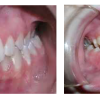

Sügav hambumus või sügav kattumine eesmiste hammaste osas

Normaalse hambumuse puhul katavad ülemised eeshambad alumisi 1/3 krooni pikkuse ulatuses ning alumiste eeshammaste lõikeserv on kontaktis ülemiste lõikehammaste suulaepoolse pinnaga. Sügavhambumuse puhul katavad aga ülemised hambad alumisi lõikehambaid rohkem...